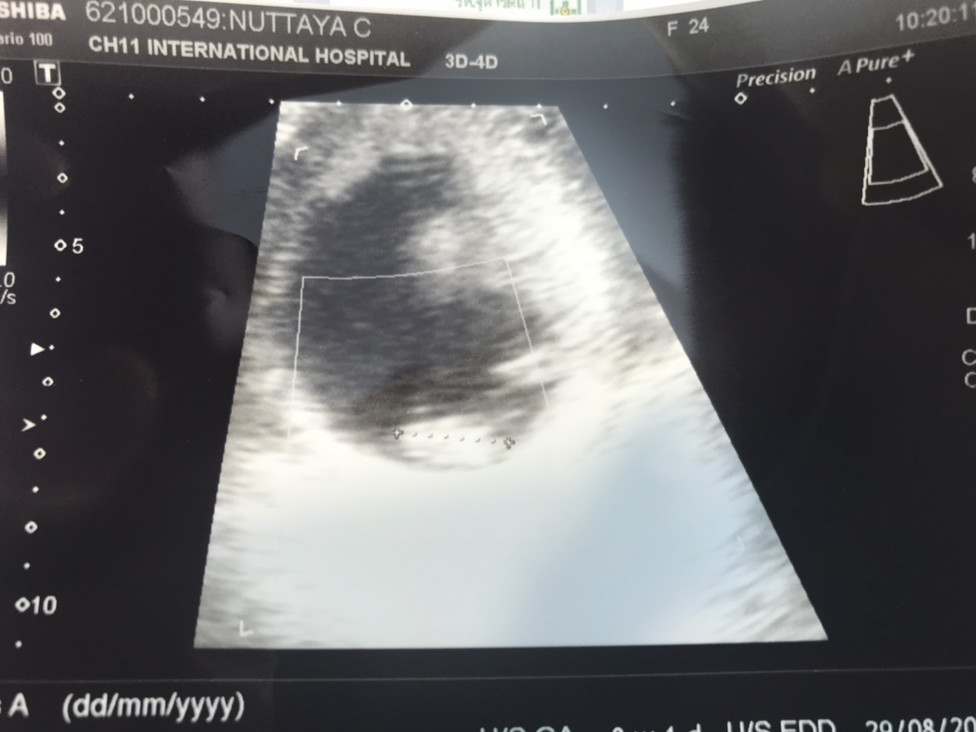

วันนี้มีเลือดออก ซาวก็ไม่เจอตัวเด็ก มีแม่ๆคนไหนที่ท้อง 9+6 วีค ยังไม่เจอน้อง แต่สุดท้ายเจอน้องบ้างค่ะ